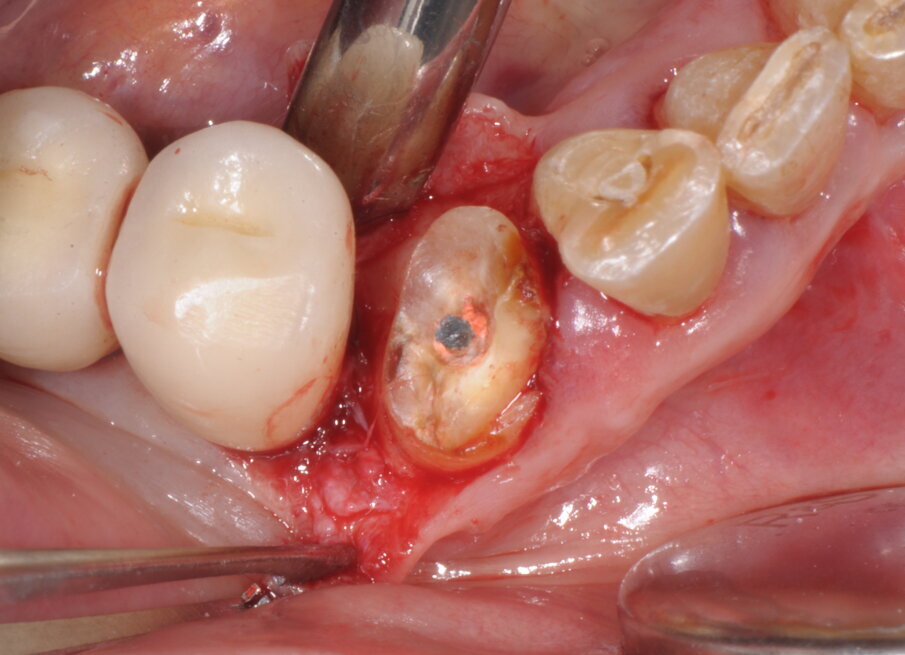

Questa separazione determina la creazione di uno spazio di manovra all’interno dell’alveolo che favorisce la lussazione, con leva manuale, della radice senza determinare compressioni a carico delle superfici alveolari, specie quella corticalizzata vestibolare, poco elastica e di scarso spessore (Figg. 4, 5; Vercellotti, 2016). Dopo accurata detersione dell’alveolo residuo integro, grazie all’effetto cavitazione della soluzione fisiologica, si è proceduto all’allestimento del sito implantare attraverso una tecnica di preparazione combinata che vede l’utilizzo sia di frese a spirale che inserti PIEZOSURGERY. In questo protocollo chirurgico di preparazione endo-alveolare del sito implantare gli inserti PIEZOSURGERY permettono con facilità la perforazione ossea e l’allestimento del sito seguendo un asse differente rispetto a quello dell’alveolo residuo, allo scopo di ricercare la maggiore stabilità primaria possibile dell’impianto (pur mantenendo un adeguato profilo di emergenza protesico).

Fig. 4

Fig. 5